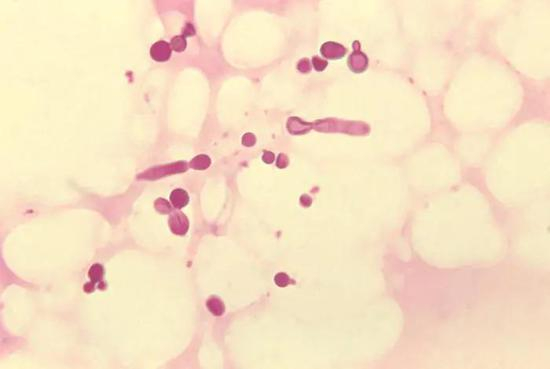

大量研究证明,马拉色菌与头皮屑的发生和严重程度密切相关。马拉色菌在头皮上的大量繁殖引起头皮角质层的过度增生,从而促使角质层细胞以白色或灰色鳞屑的形式异常脱落,这种脱落的鳞屑即为头皮屑。

放大花斑癣病患皮屑所看到的秕糠马拉癣菌丨Wikipedia

ZPT具有很强的抗菌能力,能够有效地杀死产生头皮屑的真菌(如马拉色菌),具有很好的去屑功能。此外,它在涂料等方面也有着广泛的应用。ZPT作为去屑剂已有60多年的使用历史。[2]